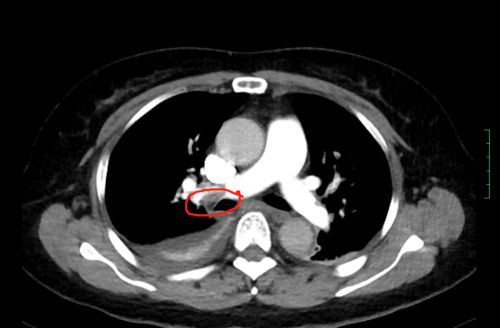

ct上可以看到,患者双侧肺动脉均有血栓形成。

值班医生立即向上级医生汇报,考虑肺栓塞可能,立即进行抗凝治疗,同时迅速陪同病人前往放射科做肺部CTA检查。放射科开通绿色通道,迅速完成检查,CT结果提示:肺动脉栓塞高度可疑。主管医生立即向科主任尹新民教授汇报。尹新民主任一边赶赴医院,一边指示值班医生请呼吸内科、心内科、介入血管外科、重症医学科、超声科等科室紧急会诊。在排除过敏性、心源性、感染性呼吸困难后,结合患者的症状,会诊专家一致考虑为“急性肺栓塞”。这是一种死亡率极高的临床急危重症,常发生于重大创伤、大型外科手术等患者,具有起病急、变化快、症状不典型的特点,极易误诊或漏诊。如抢救不及时,死亡率几乎为百分之百。

情况十万火急,尹新民主任边现场组织抢救,边将情况汇报给向华副院长,向华副院长立即调度全院各相关科室予以协助。一场与生命的赛跑由此拉开!超声科紧急为患者进行床旁彩超,找到肺动脉栓塞的“罪魁祸首”为左下肢静脉血栓。在呼吸治疗组的协助下,医护人员携带转运呼吸机快速运送方女士至介入手术室。介入血管外科紧急安排了手术医生和手术间,由张永琎副主任医师等为患者施行“肺部血管造影”,明确诊断为双肺动脉急性栓塞,随即为其实施“双肺动脉尿激酶冲击溶栓、下腔静脉滤器植入术”。术后,患者肺动脉供血明显改善,血氧饱和度立即回升,被送往重症医学一科继续治疗。